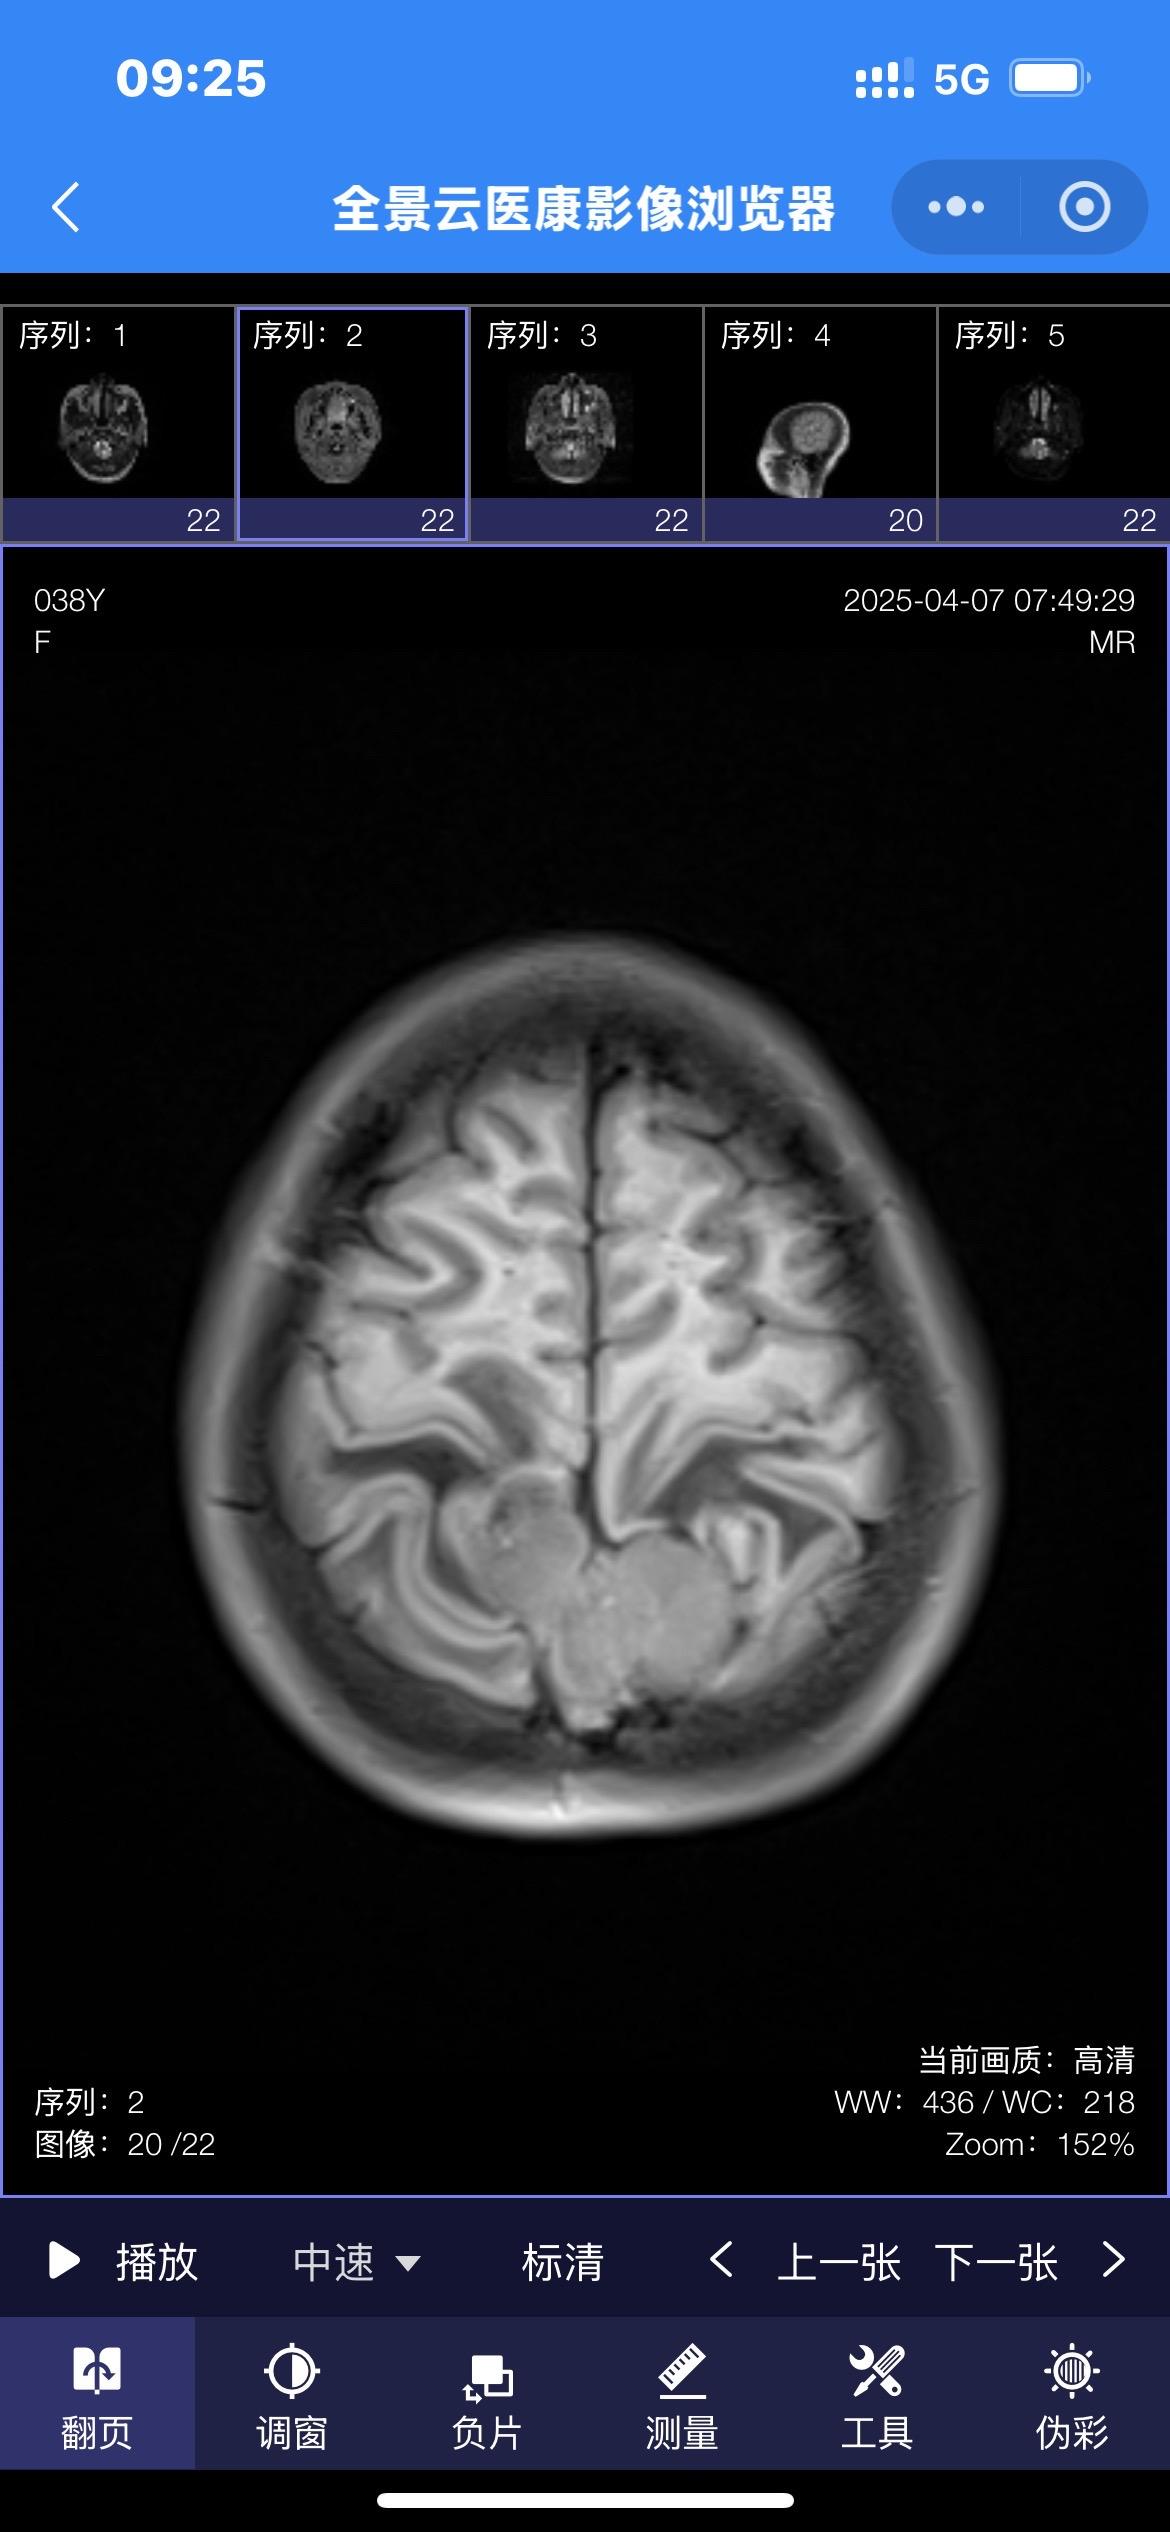

38岁女性因头痛发现脑膜瘤。脑膜瘤在女性的发病率要高于男性! 首选的治疗方法就是切除肿瘤。 有的脑膜瘤切除的难度不大,有的脑膜瘤却是难以切除干净的。 这个脑膜瘤位置就不太好,位于中央区(有重要的功能的区域),切除难度就很大!脑膜瘤手术